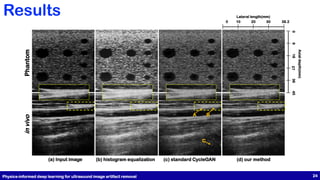

(a) Input image (b) histogram equalization (c) standard CycleGAN (d) our method

Axial depth(mm) 36 27 18 9 0 45 Phantom in vivo Lateral length(mm) 0 20 1030 38.2 (a) Input image (b) histogram equalization (c) standard CycleGAN (d) our method A B C Physics-informed deep learning for ultrasound image artifact removal 24 Results